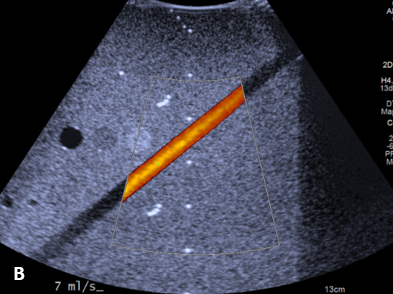

For the Doppler Mode, the analysis was in terms of flow. The performance parameters were associated with the directional accuracy of the flow, speed, direction of propagation and relative sensitivity to the depth of the signal. Flow performance was quantified using the spectral trace of the equipment itself. A flow pump was used to direct the fluid into the vessel, generating different flow rates. For each flow rate there is a conversion factor, which is supplied by the simulator manufacturer. The criterion adopted between the values specified by the manufacturer and the simulations with the simulator should not exceed ± 10% when determining the accuracy of the blood flow volume.12

The performance evaluation of the equipments showed that 15.2% of the probes had some kind of damage to the active surface. This resulted in altered signal reverberation and loss of B-Mode uniformity. This degradation reduced image quality in superficial anatomical regions between 2.0 and 3.0cm deep. The loss of uniformity was more significant for linear transducers with frequencies above 7.0MHz. It was observed that in 8.0% of the probes evaluated there were flaws in the crystals, acoustic couplers or connection cables causing image degradation for B and Doppler Modes (figure n⁰ 02).

Of the total transducers evaluated 43.95% had one or more problems related to wear and tear or misuse, resulting in a loss of image quality. Physical damage to the power cables, active surface, acoustic coupler or crystals led to degradation of the US signal. The nominal targets found in the simulator could be analyzed qualitatively and quantitatively, showing that B and Doppler Modes were directly affected. In the Doppler mode the artifacts increase the gain saturation and then change the diagnostic.